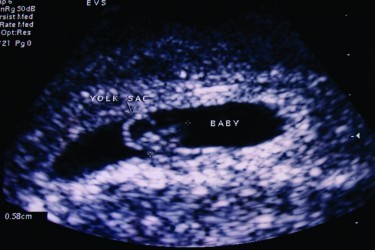

Ultrasound is one of the many available imaging modalities, enabling a substantial and unique picture of the patient. Many people are familiar with its use in obstetrics, where foetal viability, dates and anomalies are determined, but there is an ever-expanding range of medical ultrasound applications.

The simple principle of ultrasound is that high frequency sound waves, outside the human audible spectrum are transmitted through tissue. Differing proportions of the sound are either transmitted or reflected depending on particular tissue characteristics. The ratio of transmission: reflection is unique to tissue types, allowing a visual representation to be constructed.

Further advances have enabled assessment of blood flow (Doppler). Ultrasound is viewed in “real-time” allowing assessment of body function such a heart movement, blood flow and muscle and tendon movement. More recently 3D and 4D (moving3D) ultrasound clinical applications have been developed, providing even more life-like representation.